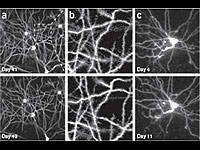

Desarrollan nueva técnica para observar neuronas continuamente